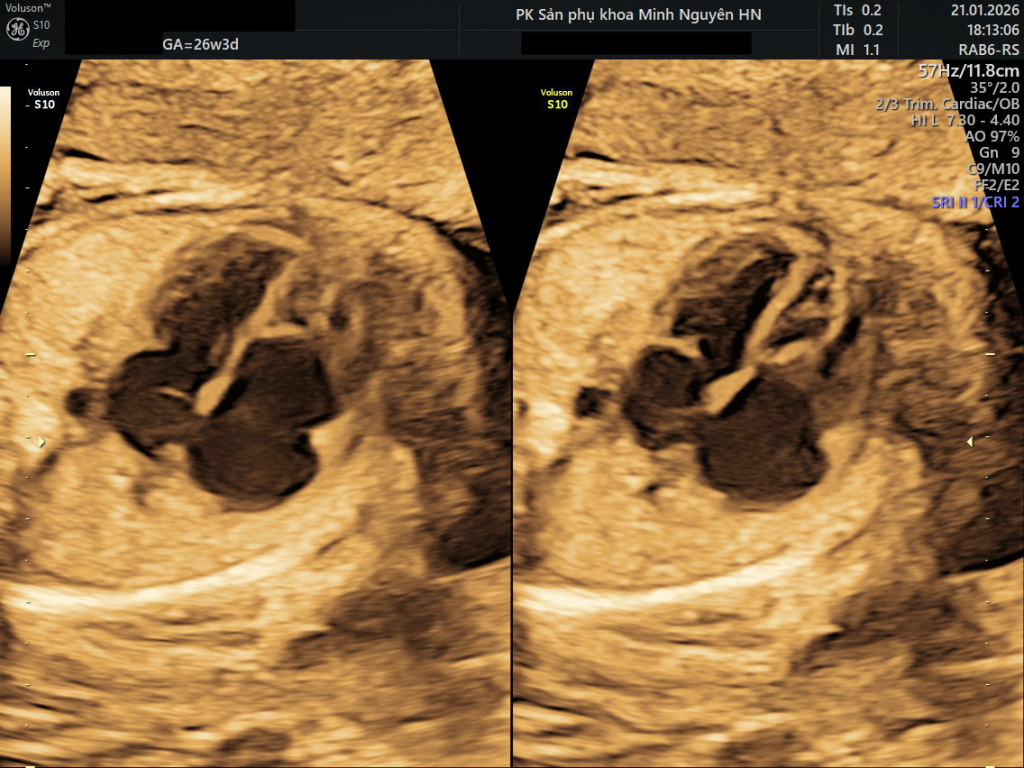

Trên siêu âm tim thai chuyên sâu, hình ảnh bốn buồng tim cho thấy lá van ba lá bám thấp xuống phía mỏm tim so với vị trí bình thường. Nhĩ phải giãn lớn, thất phải phần chức năng nhỏ lại. Doppler màu cho thấy dòng hở van ba lá mạnh. Không có dấu hiệu phù thai tại thời điểm đó.

Siêu âm tim thai là phương tiện chẩn đoán chính. Mặt cắt bốn buồng tim cho thấy lá van ba lá bám thấp hơn bình thường. Doppler màu giúp đánh giá mức độ hở van. Cần theo dõi kích thước tim, chức năng thất phải và tình trạng phù thai định kỳ.

Siêu âm tim trước sinh là phương tiện chẩn đoán chính. Mặt cắt bốn buồng tim cho phép đo khoảng cách lệch của lá van vách. Doppler màu đánh giá mức độ hở van.